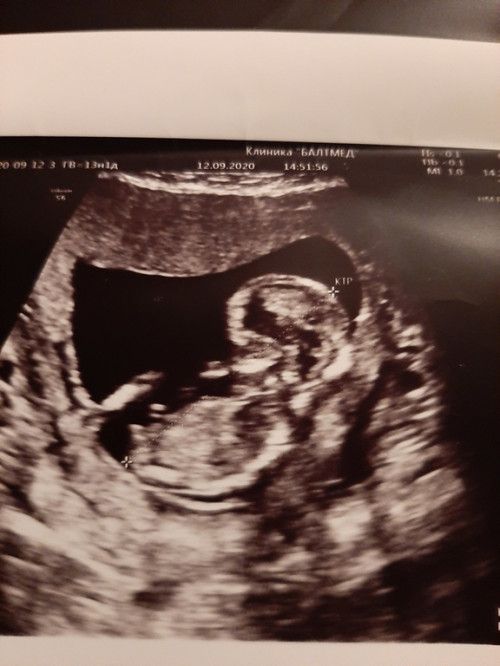

Изображение В интернете видела вот такое для первого скрининга 😄

Сходила на узи определения пола ) Экспертное узи